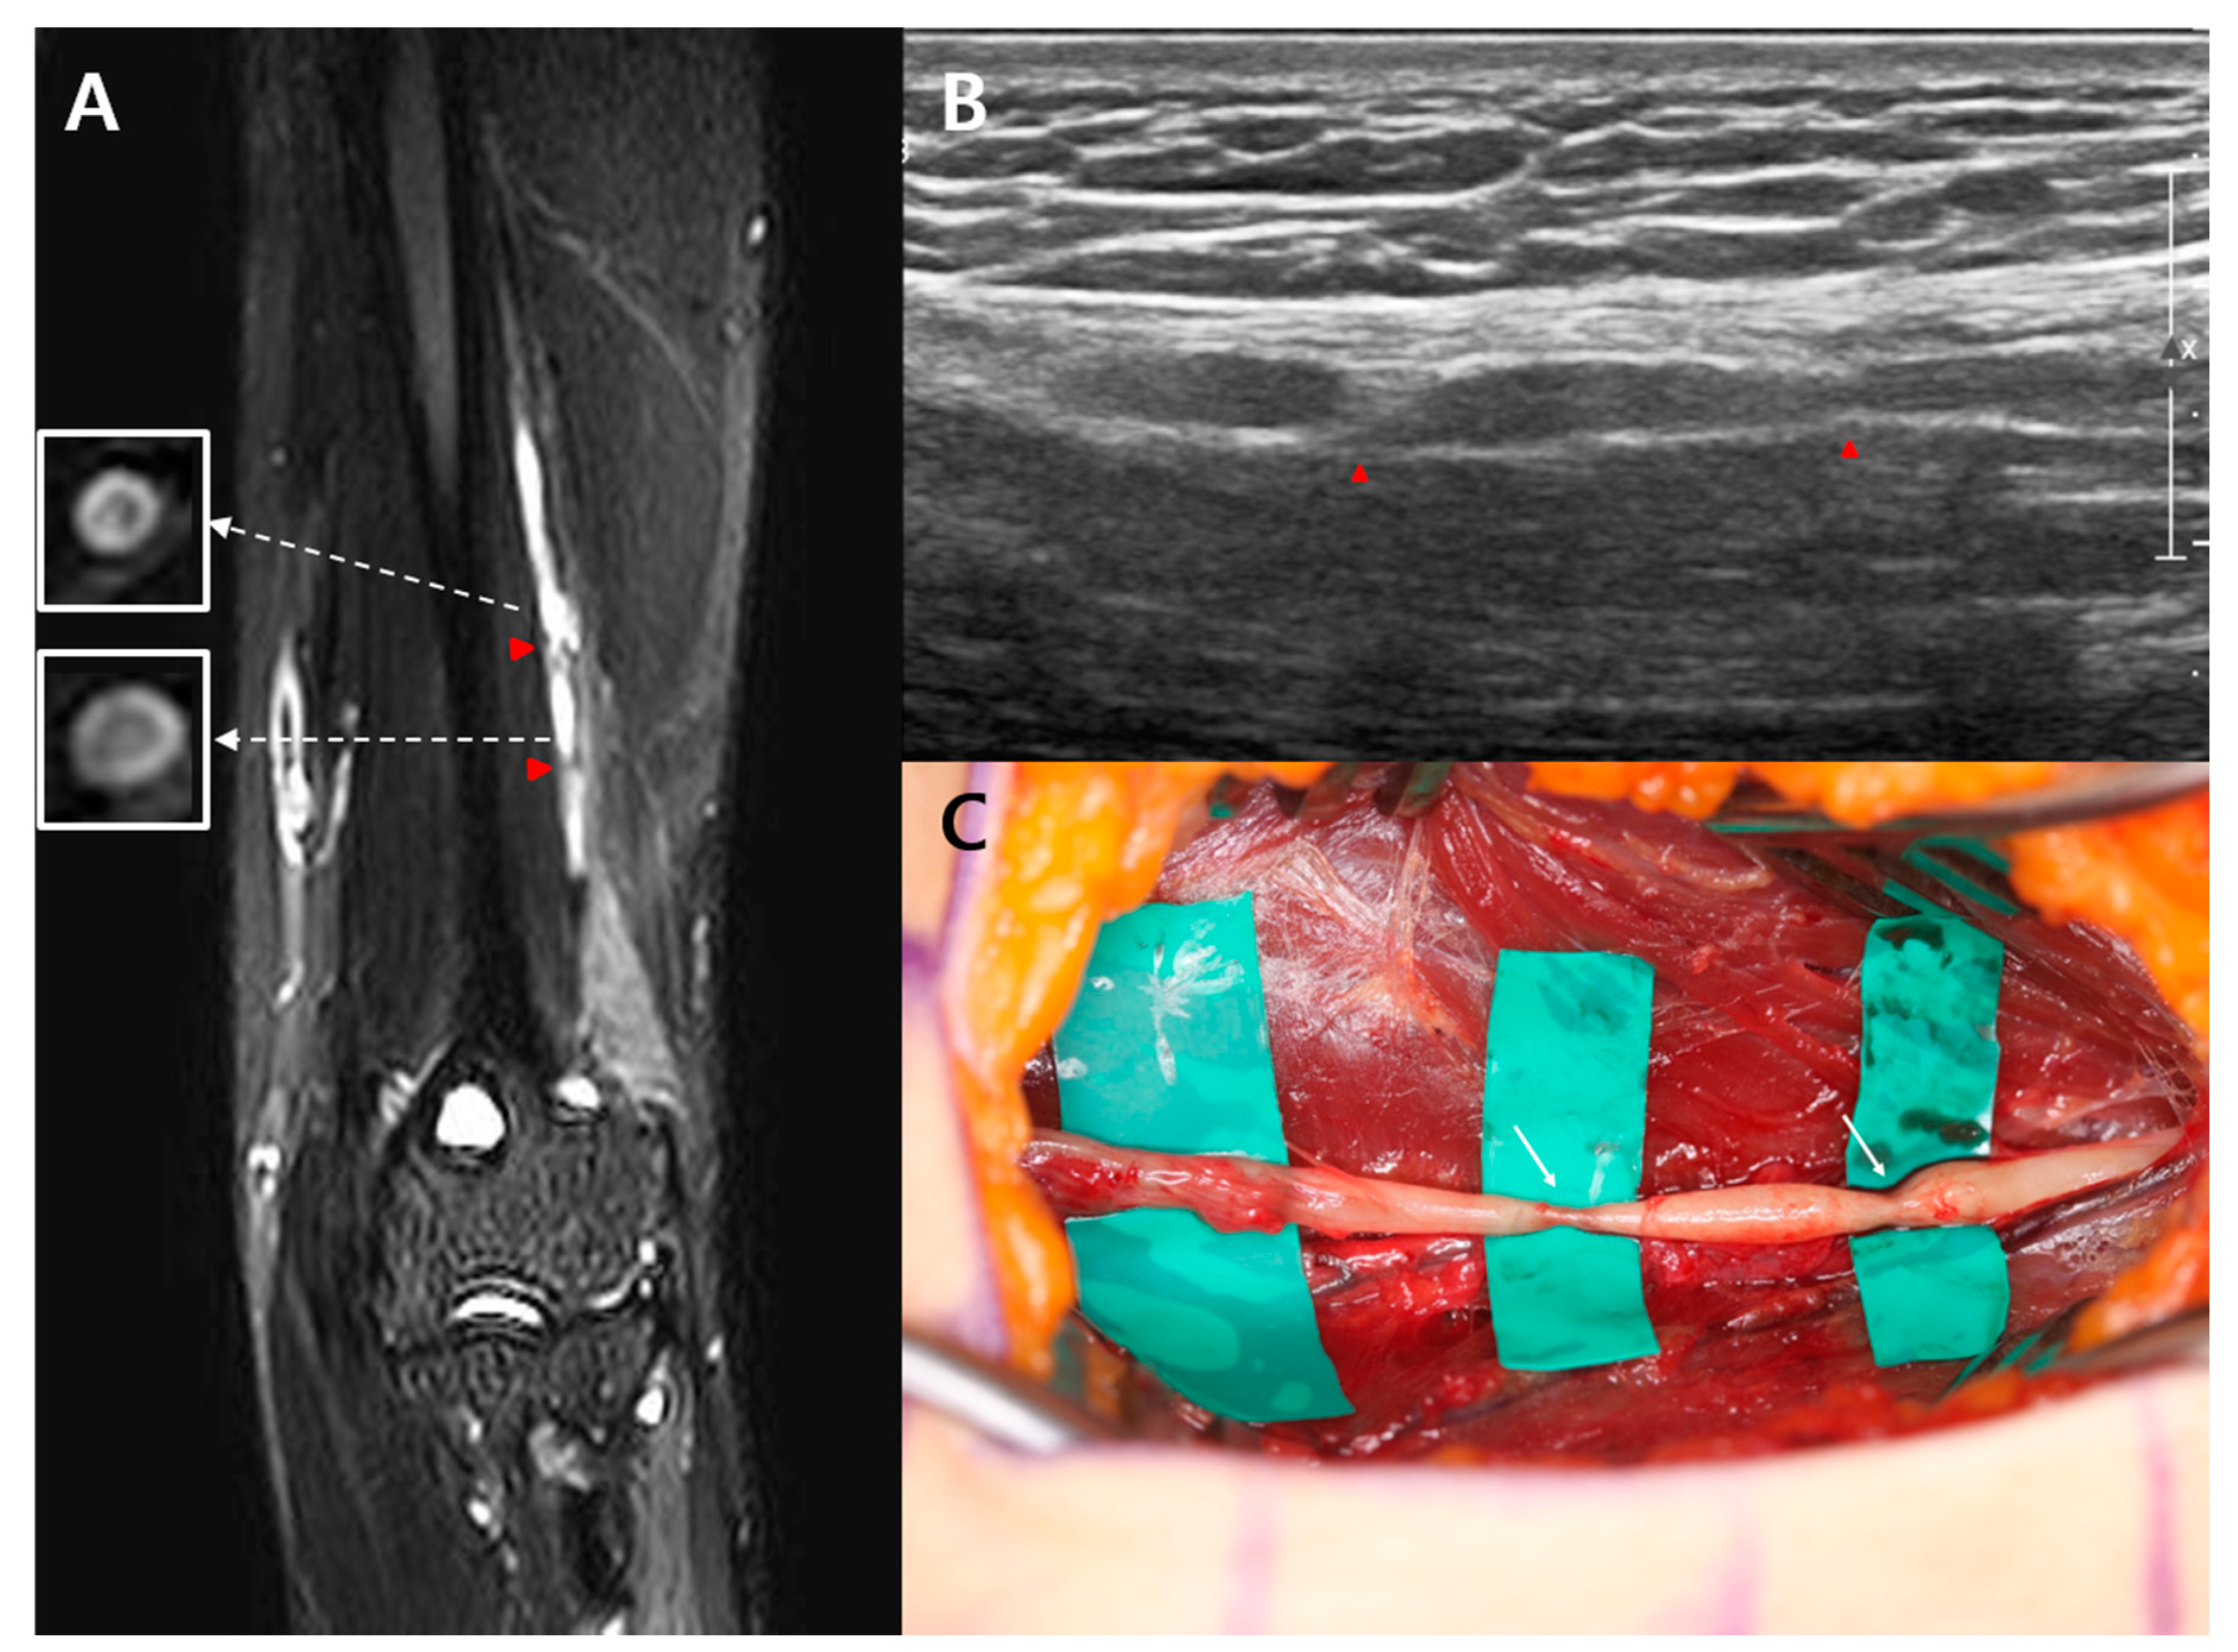

A 47-year-old man visited the department of physical medicine and rehabilitation at Samsung medical center because of a sudden onset of left wrist drop 3 weeks before presentation while working, with no identifiable cause. A day before the onset of the wrist drop, he had experienced elbow and posterior forearm pain that had persisted for a day. He had no relevant medical history. A physical examination revealed complete paralysis of the left wrist and finger extensors. No sensory deficits were observed. The patient experienced pain proximal to the elbow joint during active and passive range of motion. Approximately 3 weeks after the symptom onset, we performed cervical magnetic resonance imaging, electrodiagnostic study, ultrasound, and high-resolution MRN. The cervical MRI revealed no abnormalities. In the nerve conduction study (NCS), the compound muscle action potential (CMAP) of the left radial nerve showed a lower amplitude than that of the right radial nerve (left side: 0.9 mV vs. right side: 7.8 mV). On needle electromyography (EMG), positive sharp waves were generated in the left brachioradialis, extensor carpi radialis longus, extensor digitorum communis, and extensor indicis muscles. These muscles showed no motor unit action potential (MUAP) during volitional activity. The NCS and EMG findings indicated radial neuropathy between the left mid-humerus level and the elbow joint. To obtain the definitive diagnosis and determine the exact lesion location, a high-resolution 3-Tesla MRN, including the SHINKEI sequence, was performed. The high-resolution MRN revealed a constriction of the left posterior interosseous nerve within the epineurium of the left radial nerve, 8.9 cm proximal to the lateral epicondyle, and distal to the radial groove (Figure 1A). Further, the bull’s eye sign was observed juxta-proximal to the constriction site of the left radial nerve. A longitudinal ultrasound revealed nerve constriction in the area corresponding to the constriction observed on MRN (Figure 1B). The patient was treated with intravenous steroids (methylprednisolone 500 mg for 3 days) and tapering of oral prednisolone. Three months after symptom onset, the patient’s motor function showed no improvement, and he underwent end-to-end neurorrhaphy. The surgical findings revealed the precise location of constriction of the left radial nerve identified on MRN (Figure 1C). No muscle or other soft tissue causing nerve compression was observed. At the 6-month postoperative follow-up, the patient’s motor weakness showed no improvement.

Figure 1. Case 1: (A) High-resolution magnetic resonance neurography reveals a focal constriction (red arrowhead) of the left posterior interosseous nerve (PIN) (yellow arrows) within the epineurium of the left radial nerve 8.9 cm proximal to the lateral epicondyle. The left superficial radial nerve (white arrows) is swollen. Further, the bull’s eye sign (yellow arrow in white square) is observed juxta-proximal to the constriction site of the left PIN; (B) Longitudinal ultrasound reveals constriction (red arrowhead) of the left radial nerve; (C) Intraoperative finding confirms constriction (write arrow) of the left radial nerve.